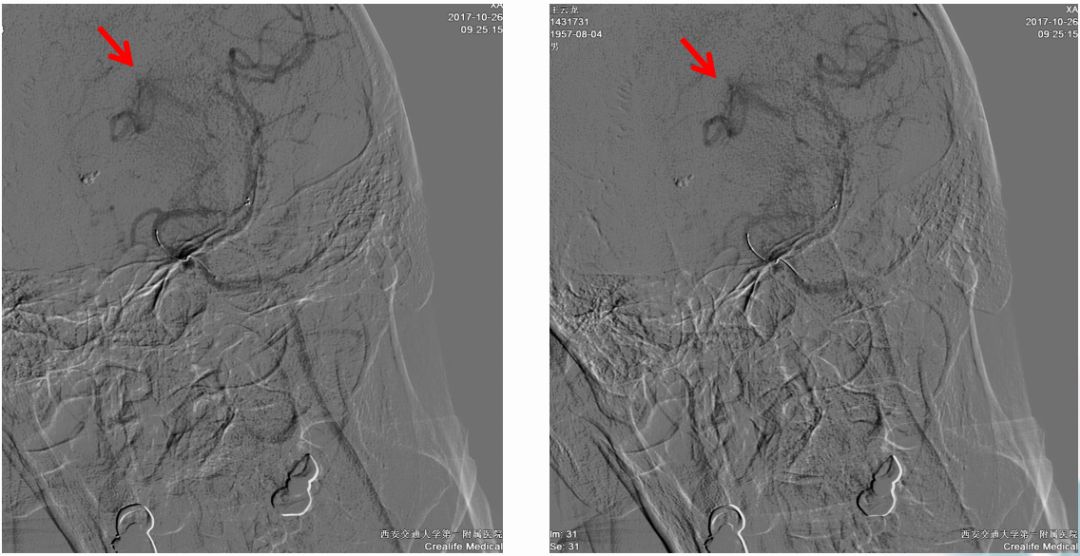

术前造影:

串联病变

ASITN/SIR 2级

支架到位释放透视图+造影图

异常早显静脉

取出栓子

术后正侧位造影图片